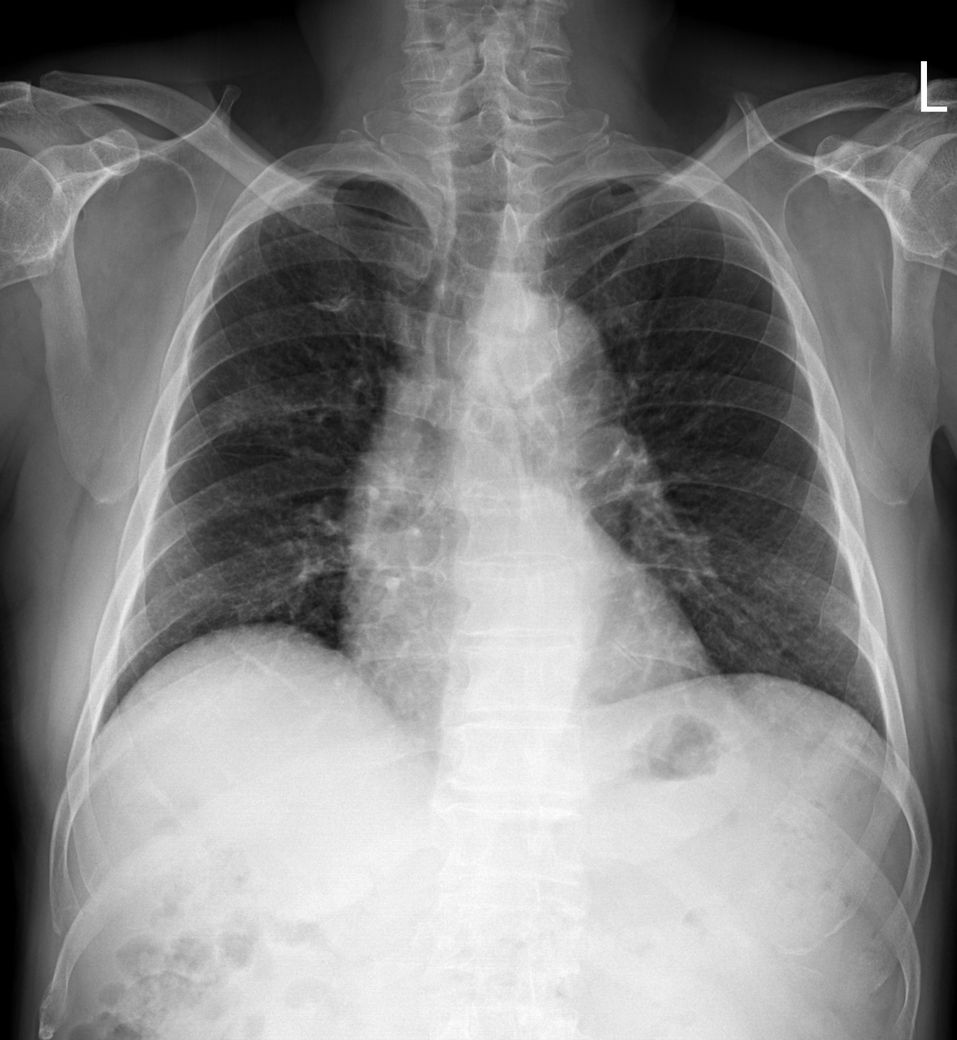

ct전 엑스레이

• 2번 째 사진